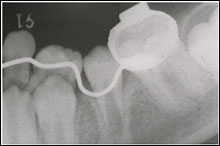

乳臼歯の骨性癒着による咬合異常

4. 下顎左側第一大臼歯の著しい近心傾斜

5. 下顎左側第二乳臼歯の埋伏低位と後継永久歯胚の位置異常

1. 歯列周長の再獲得のために下顎第一大臼歯 の直立

2. 低位乳臼歯の自然萌出なければ下顎第二乳臼歯の抜歯

3. 下顎第二小臼歯の歯列内への萌出誘導

リンガルアーチ(SLA)装置による、下顎左側第一大臼歯の整直(直立)